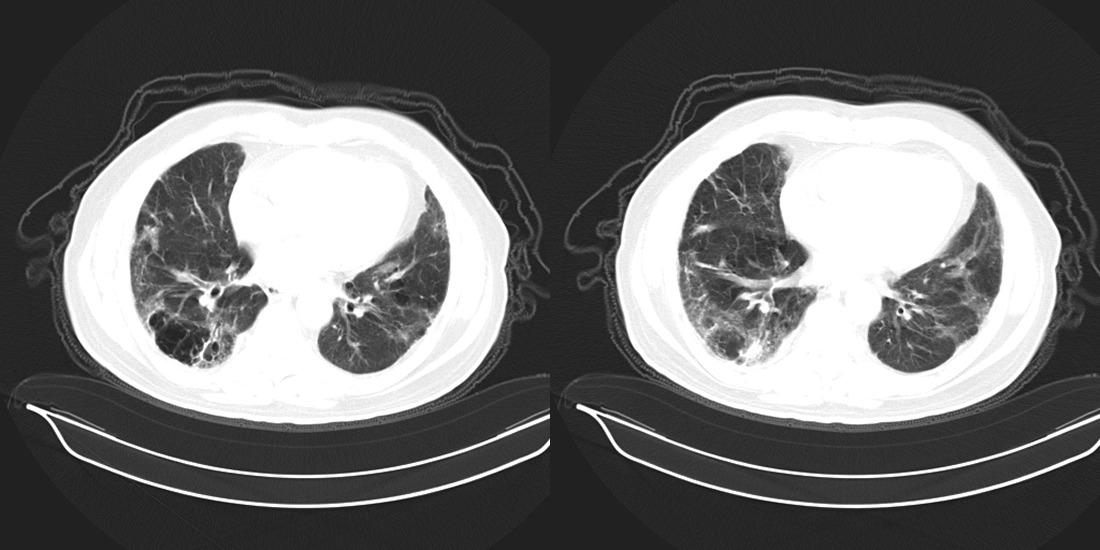

以下是引用zsl6918在2008-2-14 12:15:00的发言:[br]慢支并感染,肺气肿,肺间质纤维化,肺动脉高压。

以下是引用liuyue在2008-2-14 17:25:00的发言:[br]慢支并感染,肺气肿,肺间质纤维化,肺动脉高压 .肺大泡.[br]

以下是引用随光逐影在2008-2-15 11:10:00的发言:[br]1)慢性支气管炎并肺部感染。2)肺间质纤维化。3)肺气肿(多发性肺大泡形成)。4)肺动脉高压。